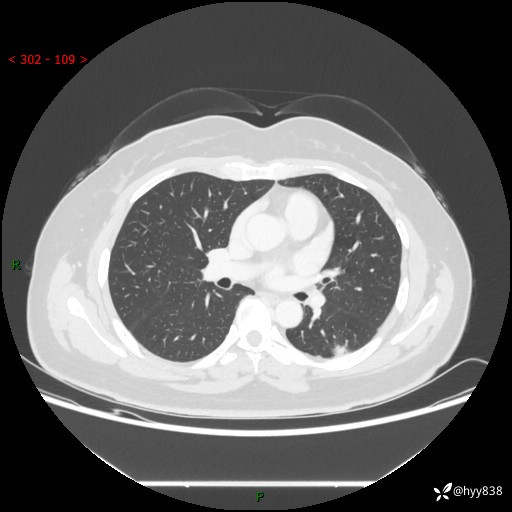

胸部CT平扫(2023.3)